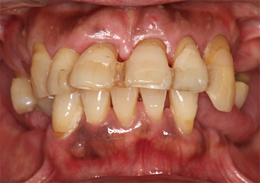

上顎のALL-ON-4(ノーベルクリニシャンを使用したフラップレス術式)

- 主訴

- 歯周病で歯がグラグラするので噛めない

- 治療内容

- 上顎に残存していた歯を抜歯。歯肉の治癒後にフラップレス手術にてインプラント埋入を行い、その場で準備してあった上顎上部構造を仮歯として、ねじ固定式で装着

- 治療費用

- 上顎ALL-ON-4:4,000,000円(税別)

- 治療期間

- 6ヶ月